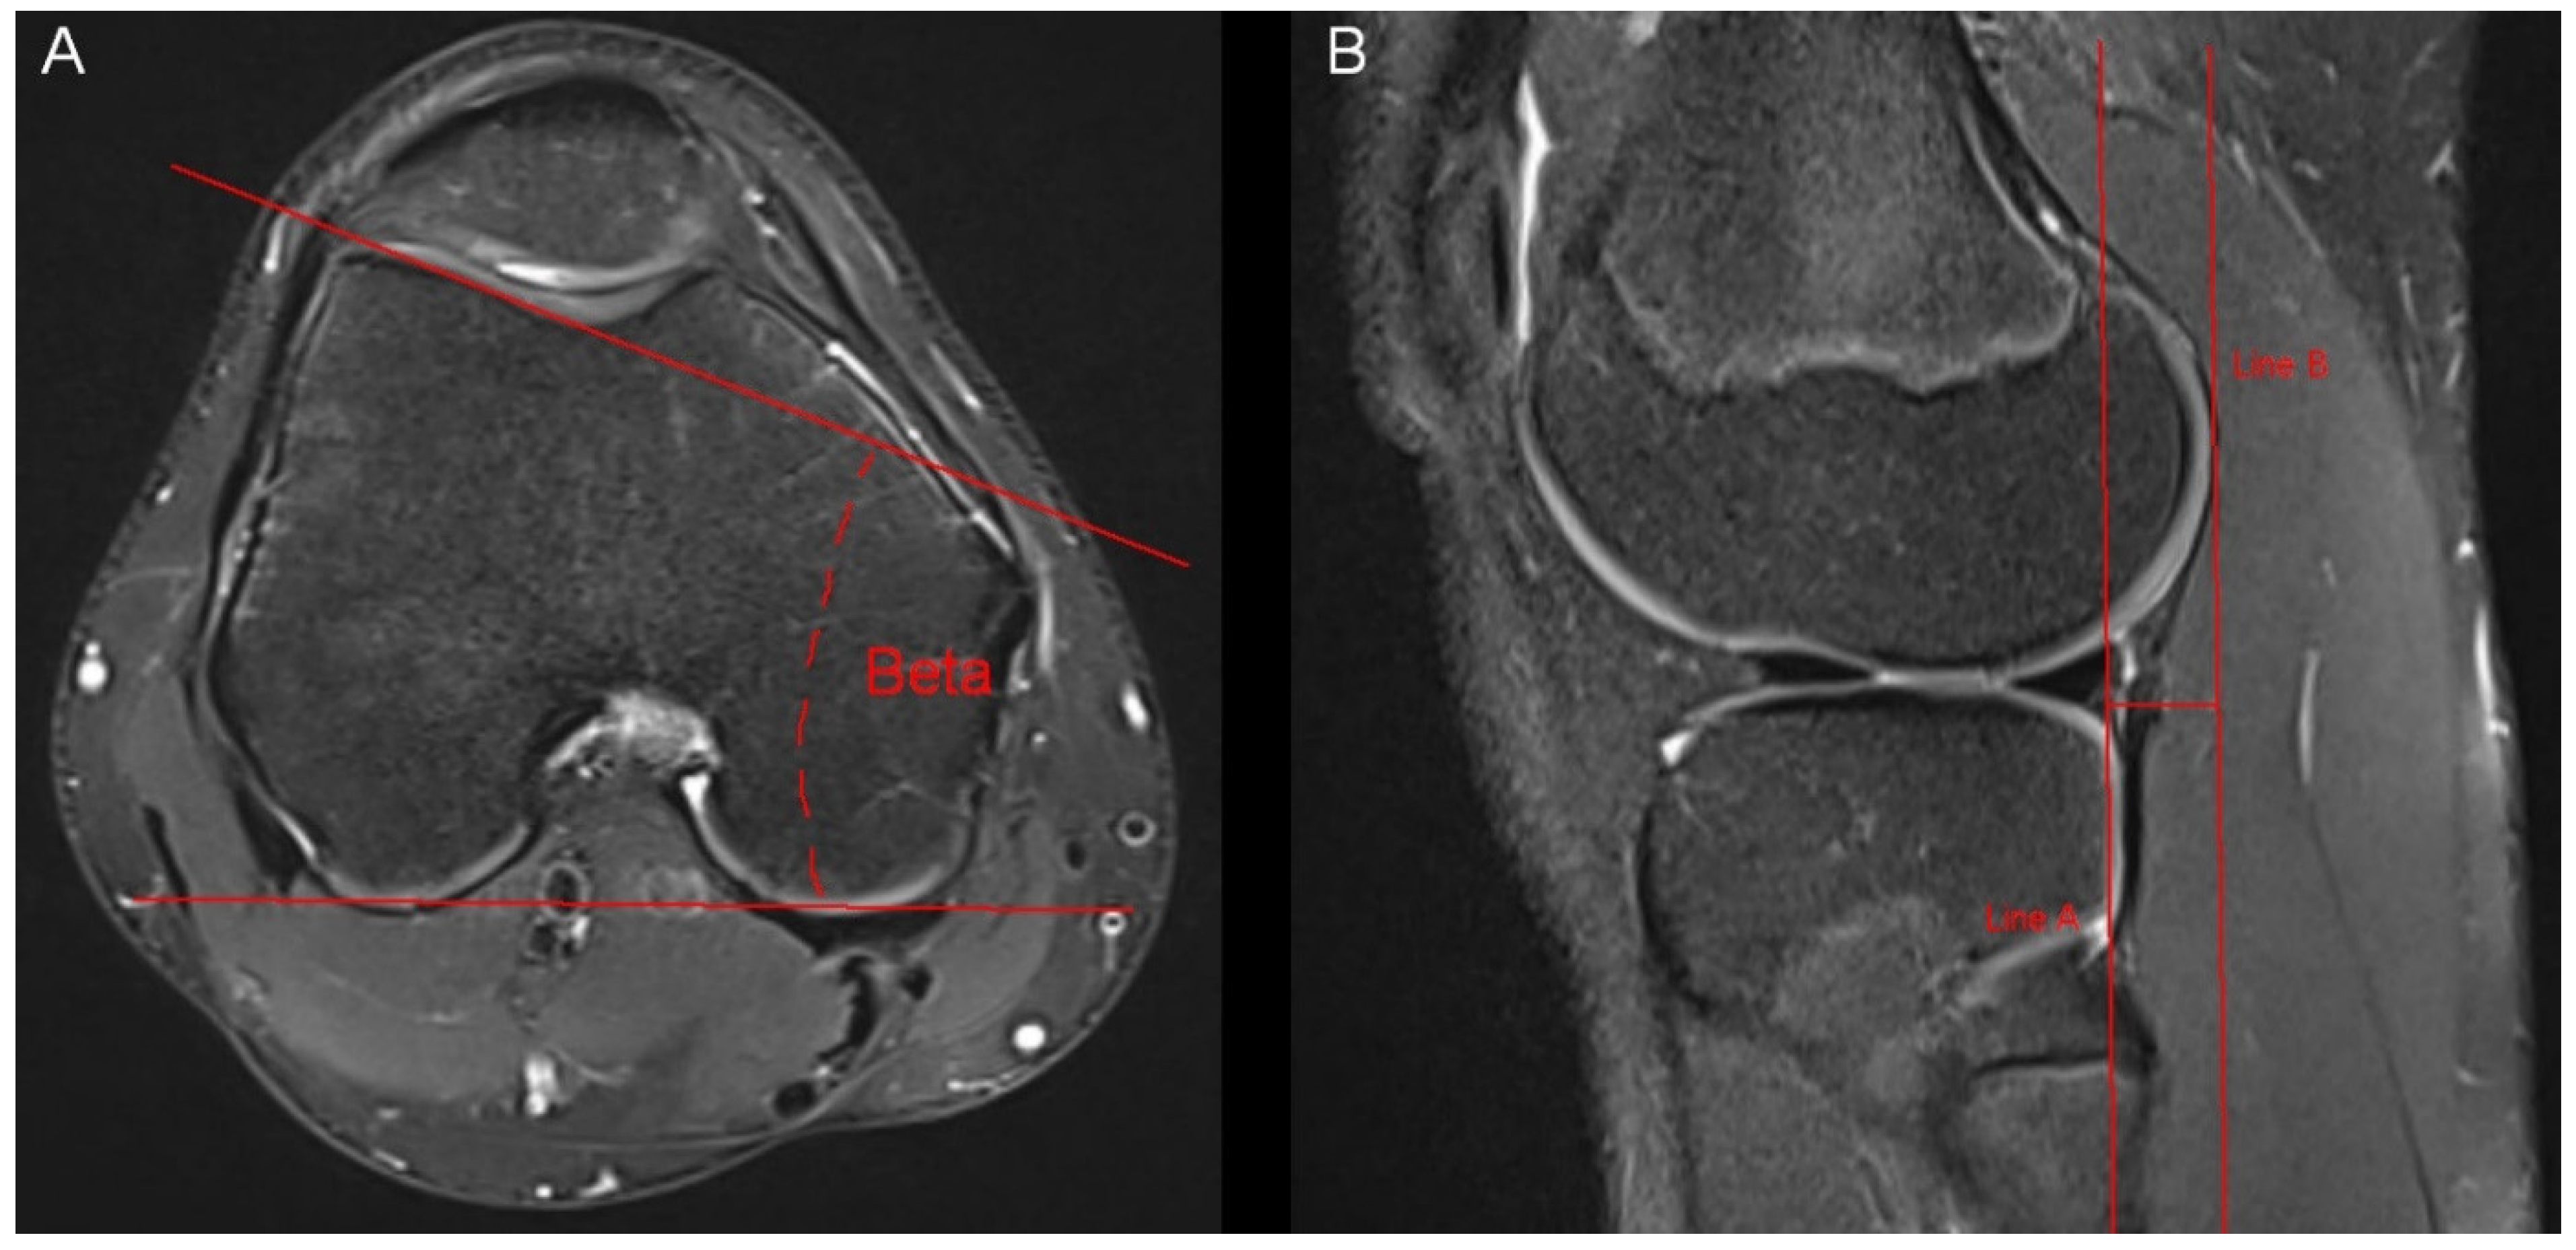

Figure 3. Measurement of the lateral trochlear inclination and the anterior tibial translocation. (A) The lateral trochlear inclination was measured through an angle (beta) between two lines. The first line was connected the posterior aspect of both femur condyles. The second line was placed on the lateral facet of the trochlea. Measurement was conducted in the axial slice offering the largest distance of the lateral facet of the trochlea. (B) The anterior tibial translocation was measured in sagittal MR-images showing the lateral femur condyle. We drew two parallel lines (line A and line B), which were also parallel to the axis of the tibia. The distance between the two lines represents the anterior tibial translocation.